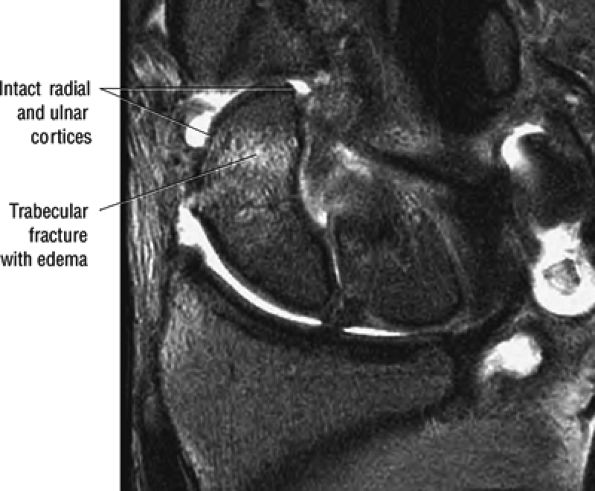

At the site of the radiolunate articulation, the distal articular surfaces of the radius and ulna are usually at the same level (i.e., neutral ulnar variance). Alternatively, the ulna may be relatively long (positive ulnar variance), leading to an ulnar abutment syndrome, or relatively short (negative ulnar variance), as is often seen in Kienböck's disease. The distal radius forms two facets that articulate with the scaphoid and lunate of the proximal carpal row. This articulation of the proximal pole of the scaphoid in the scaphoid fossa is quite congruent, and even a small degree of malrotation of the scaphoid may cause incongruent loading of the articular cartilage and subsequent degeneration (such as that which accompanies a SLAC wrist, as described by Watson and Ryu37). The lunate facet commonly becomes incongruent following distal radius fractures, especially die-punch-type fractures. The interosseous ligaments join the proximal carpal bones at their proximal edges.36